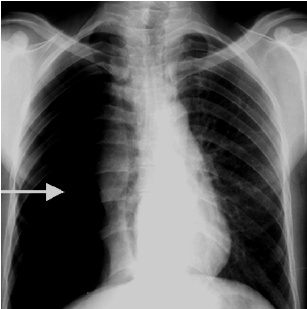

解题:箭头所指部分漆黑一片,根据公式得出气胸